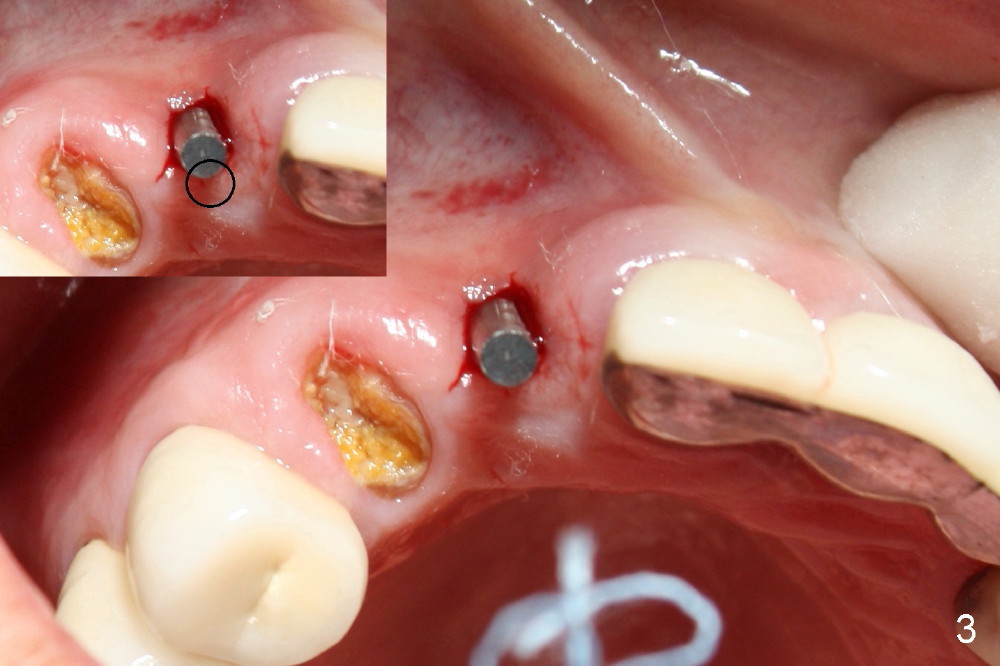

Finally the displaced implant is exfoliated itself, leaving a crater (Fig.1 arrowheads). CBCT shows the knife-edged ridge post exfoliation of the implant at the site of #7 (Fig.5, as compared to that prior to exfoliation). After using 1.5 mm pilot drill at 17 mm and 2.0 mm at 14 mm (Fig.5 insert), a 3.0x17 mm one piece angled (15 º) implant is placed (Fig.2, 10). Palatal view reveals that the implant is placed buccally (Fig.3); ideally the implant should be more palatal (Fig.3 insert: circle). Please take postop CBCT to confirm the placement. The buccal placement is partially related to the elongated tooth (Fig.4).

The reason that the implant is re-deviated buccally is that the coronal portion of the palatal plate is dense (Fig.6 *) and pushes the one piece implant buccally (Fig.7) while the latter is being inserted.